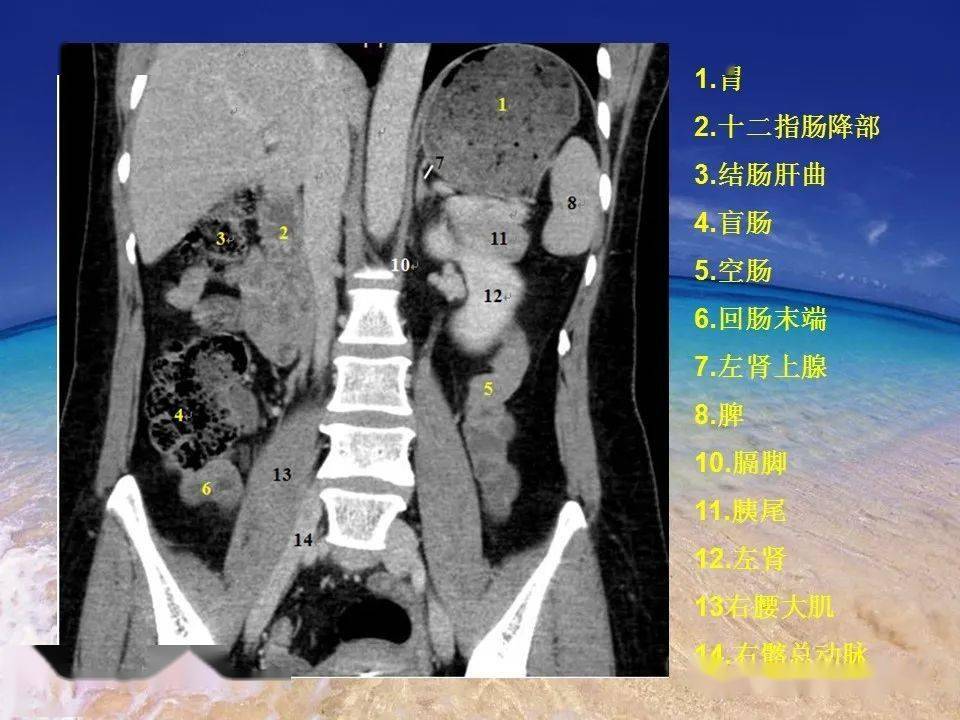

是发现异常征像的基础解剖基础ct 是诊断肠道与肠系膜损伤,穿孔的主要

图片尺寸580x574